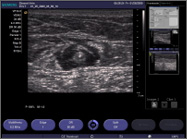

Transverse ultrasound image of tumescent anesthetic fluid surrounding centrally located great saphenous vein and laser fiber/sheath.

| Transverse ultrasound image of tumescent anesthetic fluid surrounding centrally located great saphenous vein and laser fiber/sheath. |